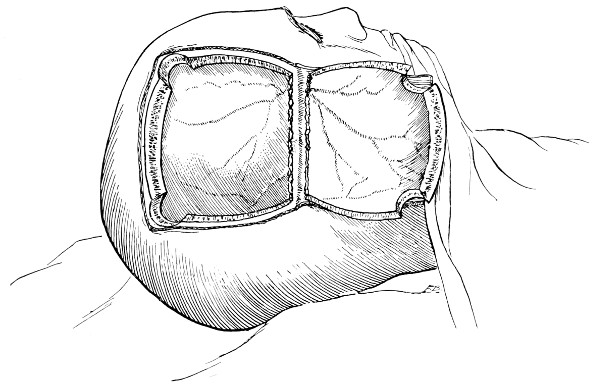

Fig. 18. Second Stage in the Formation of an Osteoplastic Flap. The bone-flap turned down and the dura mater exposed.

Fig. 19. Third Stage in the Formation of an Osteoplastic Flap. The dural flap turned down and the brain exposed. Note the relation of the scalp, bone, and dural incisions to one another.

Opening the dura mater.

Reference has already been made to the great importance of opening the dura in such a manner as to avoid injury to the underlying superficial cerebral vessels (see p. 19). It may be incised in a crucial manner or by flap-formation. Flaps are usually to be preferred if the surgeon desires to have the widest possible view of the brain surface. In the formation of the flap, advantage should be taken of the vessels that minister to its vitality. Thus, in the lateral region of the head, the base lies below, the middle meningeal artery supplying the flap. Under special circumstances, the blood-supply may be disregarded; the flap never sloughs, so far as my experience goes.